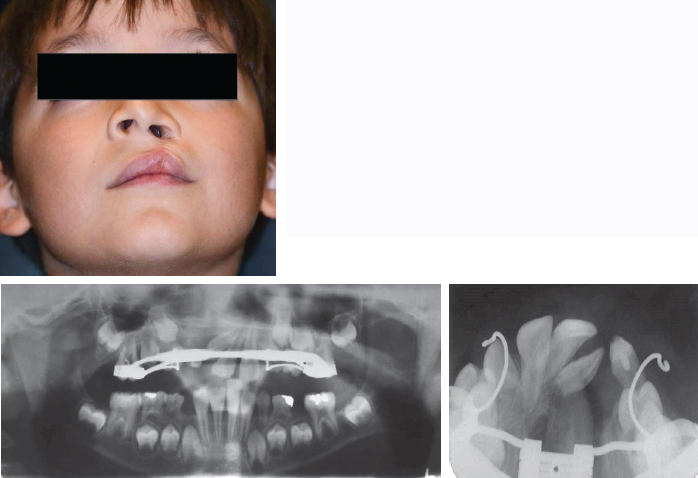

Clefting of the maxilla and alveolus results from a failure of fusion of several key components of the facial structures during the first trimester and typically includes components of the maxillary processes, median nasal process, and palatal shelves.1 When one or several of these components fail to fuse, a variety of clefts can be seen. Each bone and soft tissue defect is reconstructed in a particular fashion and is staged based on growth, functional needs, and aesthetic concerns. Despite successful lip repair and closure of the hard and soft palate during infancy, a residual nasolabial fistula and bony cleft defect that involves the alveolar ridge, maxilla, and piriform rim will remain.2,3 These residual deformities are most often addressed by secondary bone grafting performed during the mixed dentition stage of middle childhood (6 to 10 years of age).2,3 The objectives of bone graft reconstruction of the cleft maxilla are to establish adequate bony matrix for eruption of the permanent cuspid tooth, to close any residual alveolar oronasal communication, to establish continuity of the maxillary ridge, and to improve the underlying support of the nasal base (Fig. 69-1). In the case of bilateral cleft lip and palate, an added benefit of bone graft reconstruction is stabilization of a mobile premaxillary segment.

Fig. 69-1 This child with a left unilateral cleft of the lip and palate exhibits the typical depressed piriform rim and maxilla in the area of the bony cleft. Although rhinoplasty can be used in an attempt to provide symmetry to the nose, the primary lack of structure is associated with the maxillary and alveolar cleft. The defect in the bone at the alveolar level may be fairly small, but attention is required at the remainder of the maxilla to provide an adequate reconstruction to achieve all of the goals. Note the proximity of the central incisor to the cleft.